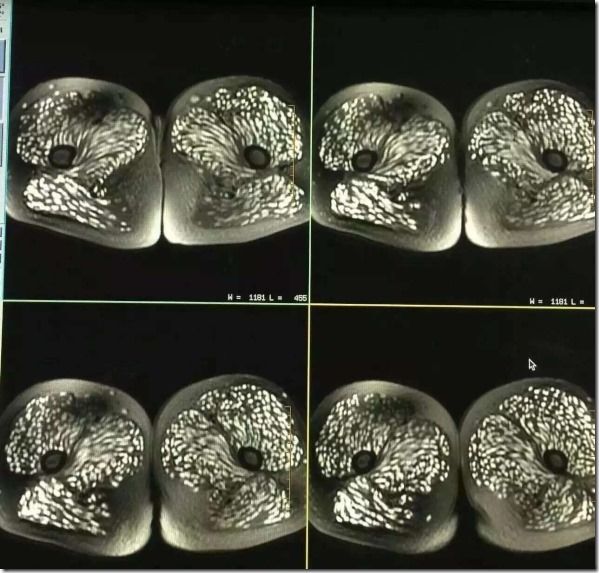

病院では頭部MRIと全身CTスキャンが行われたが、その検査結果は専門家さえも驚く衝撃的なものだった。それもそのはず、女性の全身はすでに無数の寄生虫に侵されており、大脳や顔面の筋肉にさえも感染が見られるひどい有様だったからだ。

医師の話では、女性の体内の寄生虫の一部はすでに死に、石灰化しており、全身の痛み以外に眼球突出や網膜出血といった症状も見られたとのこと。治療はすぐに行われたものの、一部の寄生虫は体外に排出されず、女性には後遺症が現れる可能性も否めないという。